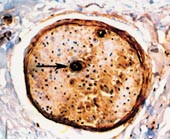

Pasient 1. 70 år gammel mann som fire år tidligere ble utredet for lungefortetninger, uten at det var holdepunkter for sarkoidose, tuberkulose eller malignitet. Han var ellers tidligere frisk. Han ble innlagt pga. åtte måneders sykehistorie med tiltakende svie, smerter, parestesier og brenning i begge underekstremitetene, med ustøhet og ortostatisme samt avmagring og vekttap. Han hadde ikke misbrukt alkohol og ikke hatt diabetes mellitus eller vitamin B12-mangel. Klinisk hadde han normale dype senereflekser og vibrasjonssans, hyperestesi/-algesi og allodyni kombinert med moderate pareser i underekstremitetene og betydelig ortostatisk blodtrykksfall. Omfattende utredning viste ikke tegn til malignitet eller annen kronisk infeksiøs eller inflammatorisk sykdom. Elektromyografi (EMG) og elektronevrografi (ENG) viste sensorisk-motorisk polynevropati av blandet demyeliniserende og aksonal type. Det var ikke noen sikre responser å registrere fra de sensoriske nervene i beina, men ledningshastighetene i de motoriske nervene i beina var ca. 37 m/s. Spinalvæskeanalyse viste ingen leukocytter, og spinalprotein var 1,27. Det ble påvist to serumlike IgG-bånd i spinalvæske, samt to bånd i urinen. Han utviklet biventrikulær kardiomegali i løpet av det siste året. Pasienten ble behandlet med høydose steroider og plasmaferese, uten effekt. I nervebiopsi ble det påvist hyalint materiale (fig 1), identifisert som amyloid. Pga. dårlig allmenntilstand ble kjemoterapi ikke instituert.